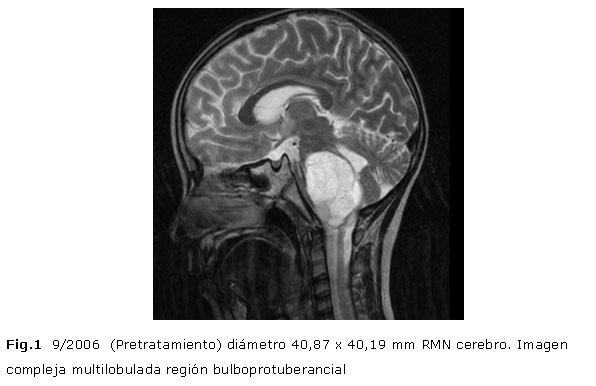

Volver a los detalles del artículo Anticuerpo monoclonal h-r3 en el tratamiento de tumor de tallo cerebral: presentación de un caso / Monoclonal antibody h-R3 in the therapy of brainstem tumour: a case presentation